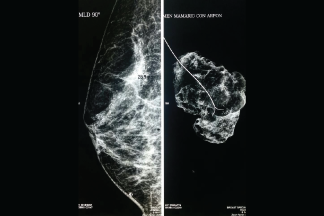

Marcaje de arpón

El estudio consiste en la inserción de una aguja especial en el área específica de la mama donde se localiza la lesión o masa, obteniendo una pequeña muestra del tejido, la cual es enviada a un laboratorio especializado donde se analiza la muestra y se determina la presencia o no de cáncer.

La aguja es insertada por un doctor especializado y certificado guiándose en tiempo real por las imágenes proporcionadas por mastógrafo o por ultrasonido para tomar la muestra exactamente de la lesión o masa. Este procedimiento es de mínima invasión, el cual no requiere hospitalización.